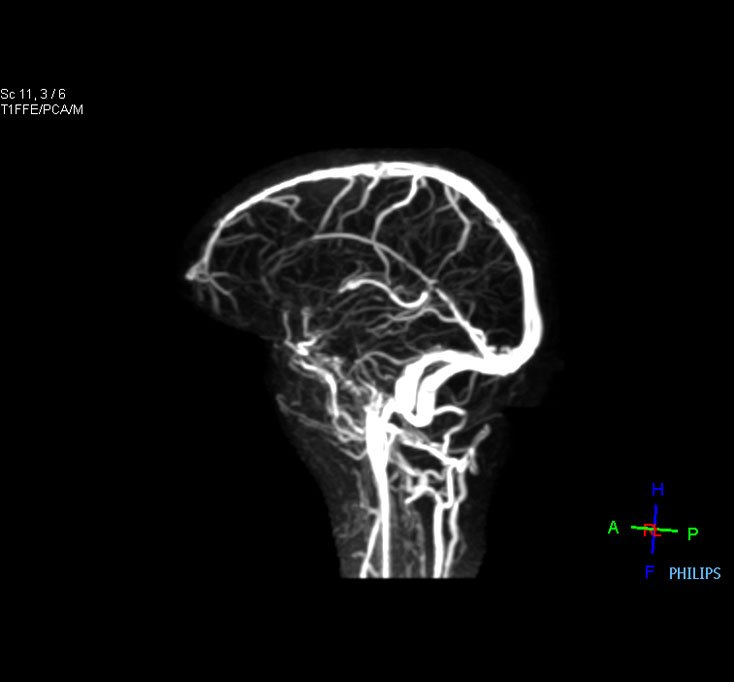

Brain Venography